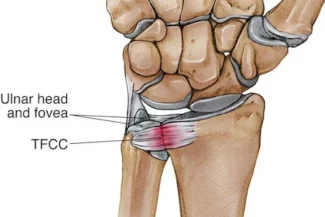

Réparation du ligament triangulaire

L’ablation de kystes du poignet sous arthroscopie est une intervention chirurgicale qui vise à enlever les kystes qui se sont formés dans ou autour de l’articulation du poignet en utilisant une technique d’arthroscopie. L’arthroscopie est une procédure moins invasive dans laquelle de petites incisions sont pratiquées, et une caméra minuscule (arthroscope) est insérée pour visualiser l’intérieur de l’articulation en temps réel.